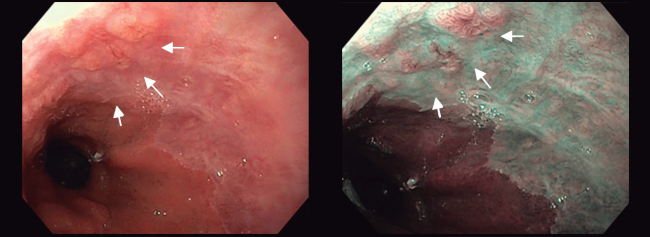

Para la descripción de las lesiones visibles en el EB se utiliza la misma clasificación de París que para los pólipos del colon. Además, debe describirse su localización en función de la distancia a la arcada dentaria y su situación en la circunferencia esofágica. La utilización de endoscopios de alta definición mejora la detección de lesiones pero es recomendable utilizar técnicas de cromoendoscopía virtual o con ácido acético 2% (figura 2). Este último provoca un cambio de coloración inmediato pasando del color asalmonado típico del EB al blanco y es útil para identificar las áreas sugestivas de displasia (que son las zonas que recuperan el color de forma precoz).